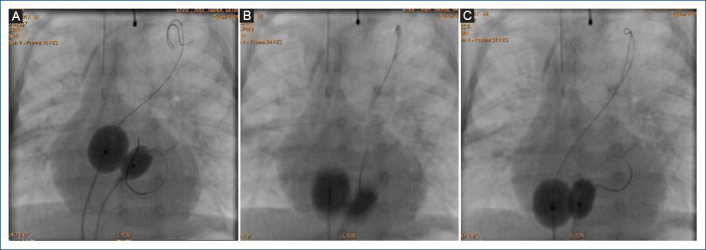

Objectives: Balloon atrial septostomy (BAS) is a palliative procedure mainly for newborns with transposition of the great arteries, currently, this procedure has a class IA recommendation. However, in some cases, this procedure does not achieve an adequate interatrial defect, due mainly to a thickened interatrial septum, this situation led to the development of various techniques to tackle this problem. Therefore, we made a modification to the original technique using two balloons simultaneously instead of one. The objective of this study is to analyze the results of this new modification to the traditional technique (with one balloon) as an alternative for cases with thickened interatrial septum.

Results: Six patients were identified (median age 35 days, median weight 3.4 kg, median size of atrial septal defect before procedure 2.6 mm). All patients underwent to this modification of the BAS with good results and without complications. The modification has some advantages: including to avoid the using of cutting devices or stent placement. In addition, we share the description of this new technique, titled: double "dynamic" BAS.

Conclusion: This brief evidence shown that this modification of de original technique is easy, safe, and cost-effective for cases with a thickened interatrial septum.